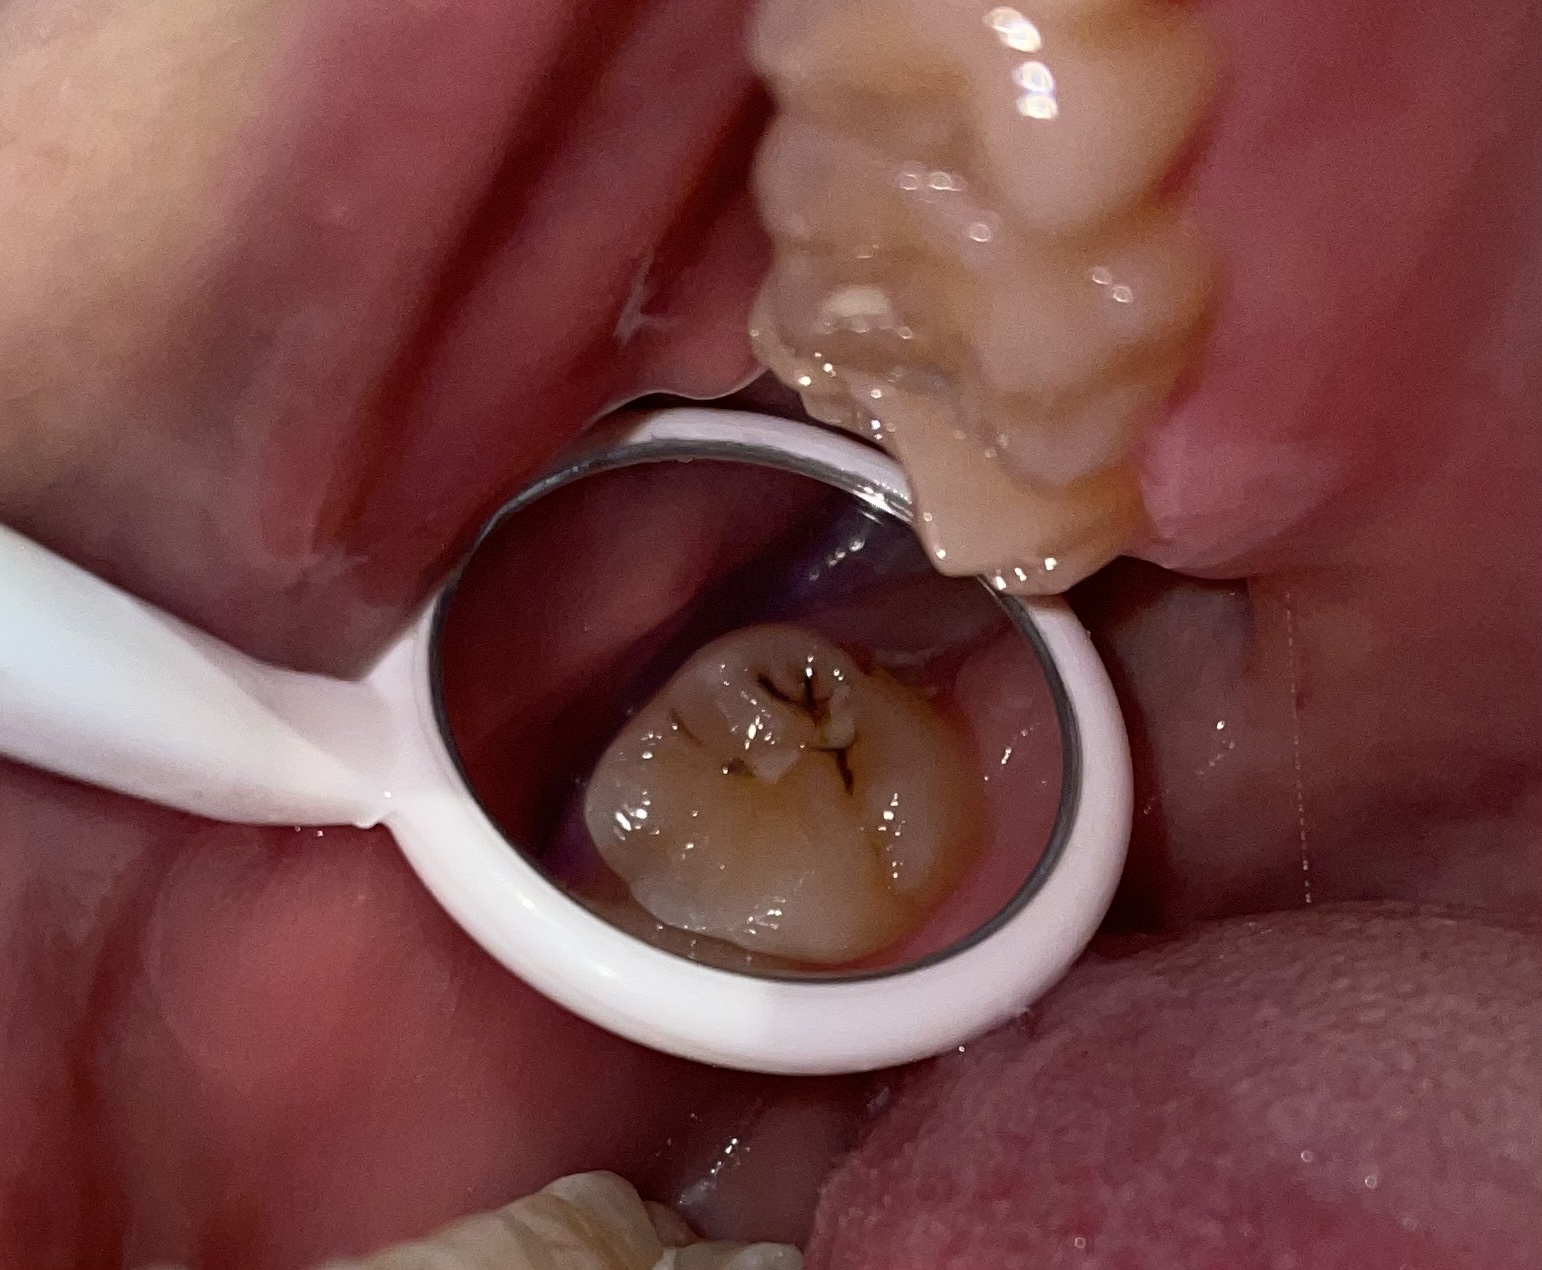

Heute habe ich festgestellt, dass ich bei einer der hinteren oberen Backenzähne in den Fissuren (die bei mir relativ tief sind) solche Ablagerungen habe. Es ist schwarz, tut bisher allerdings nicht weg und ist auch nicht kälteempfindlich oä. Achso: Das Weiße auf dem Zahn stammt noch von einer Versieglung von vor ein Jahren. Zu mir: Ich rauche nicht, trinke aber jeden Tag Kaffee.

ist nur zahnstein und sollte nicht entfernt werden (bester karies schutz!)